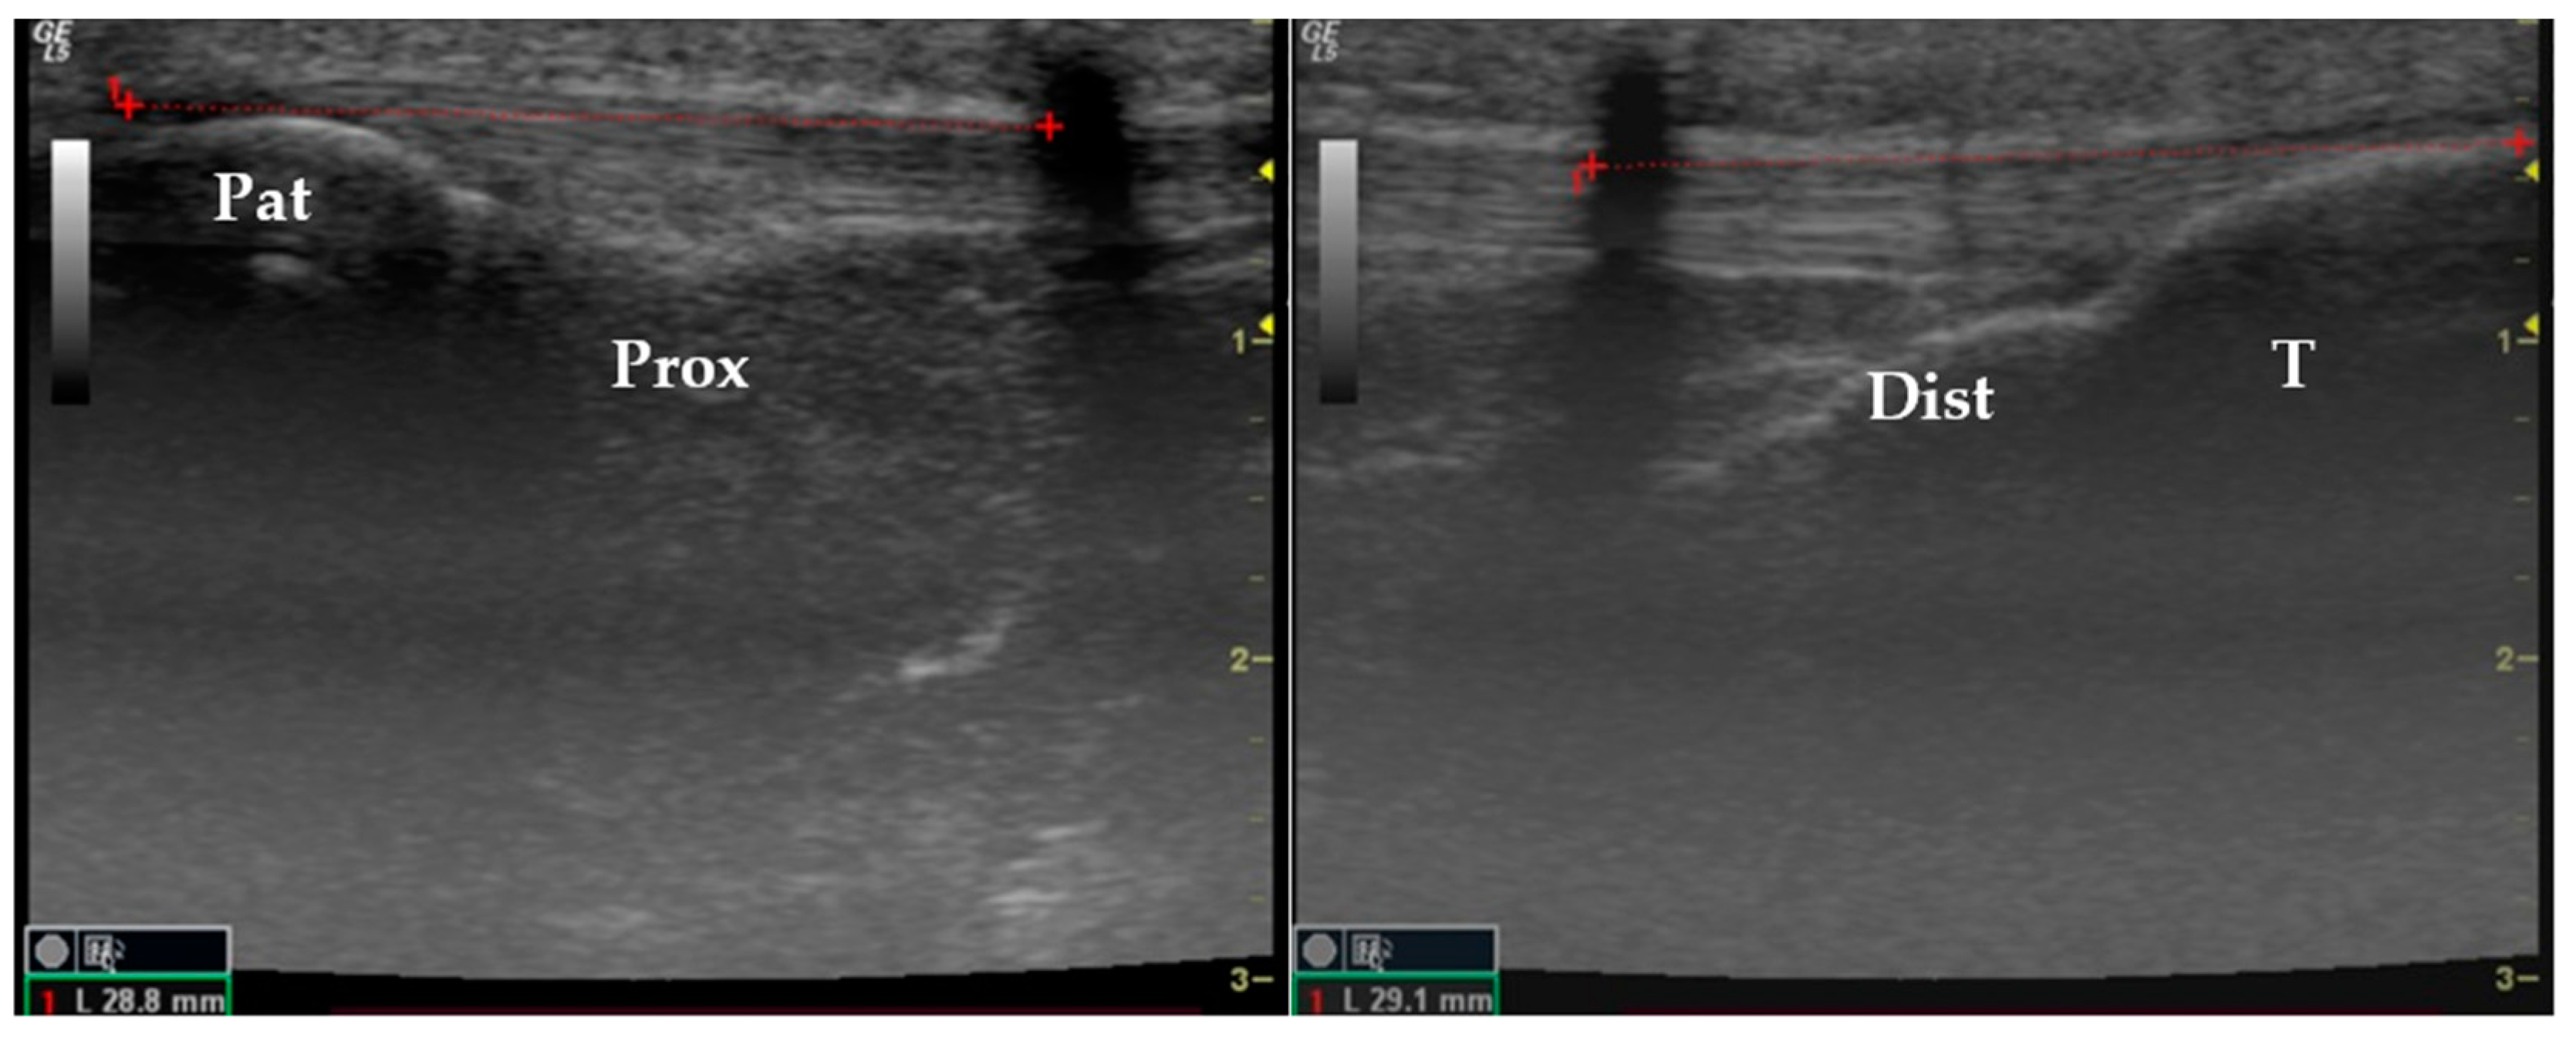

2.2. Study Design

2.3. Data Collection